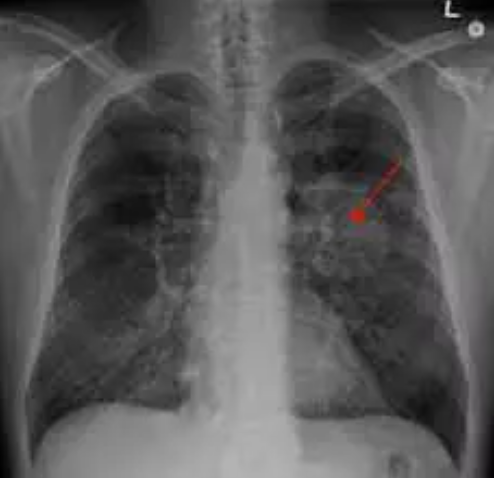

Yapılan incelemeler sonucunda, Xu'nun sağ akciğerinde yaklaşık 1 santimetrelik kitle fark eden doktorlar, bunun kötü huylu tümör olabileceği ihtimali üzerinde durdu.

Doktorlar, kanser olabileceği düşündükleri Xu'ya tam teşhis koyabilmek için akciğer dokusundan parça alarak testler yaptı. Yapılan testler sonucu, doktorların kötü huylu tümör sandığı kitlenin acı biber parçası olduğu anlaşıldı.

Biber parçasının, 2 yıl önce yemek yediği sırada boğazına kaçtığını ve şiddetli şekilde öksürdüğünü hatırlayan Xu'nun yaşadıkları Çin'deki sosyal medya platformlarında oldukça ilgi çekti.